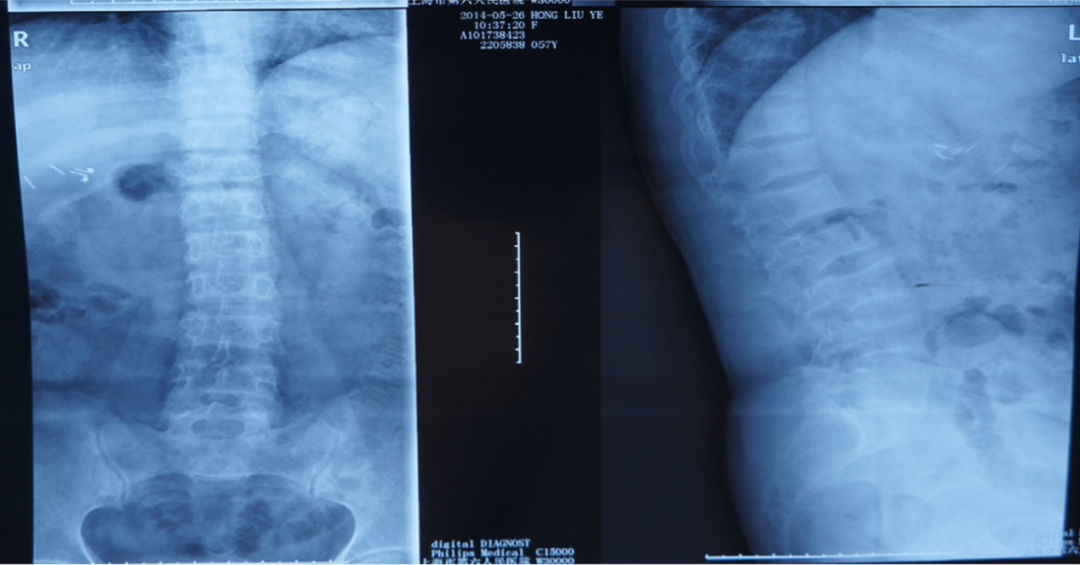

X线检查:胸腰椎多发压缩性骨折伴骨质疏松。

诊断:低磷性骨软化(肿瘤性可能)、继发性甲状旁腺功能亢进。

治疗:中性磷溶液、骨化三醇,术后随访观察。

术后两年:出现磷酸盐尿性间叶肿瘤(PMT),血FGF23显著下降,血磷正常。

X线检查:L2压缩性骨折椎体骨质疏松,头颅未见异常。